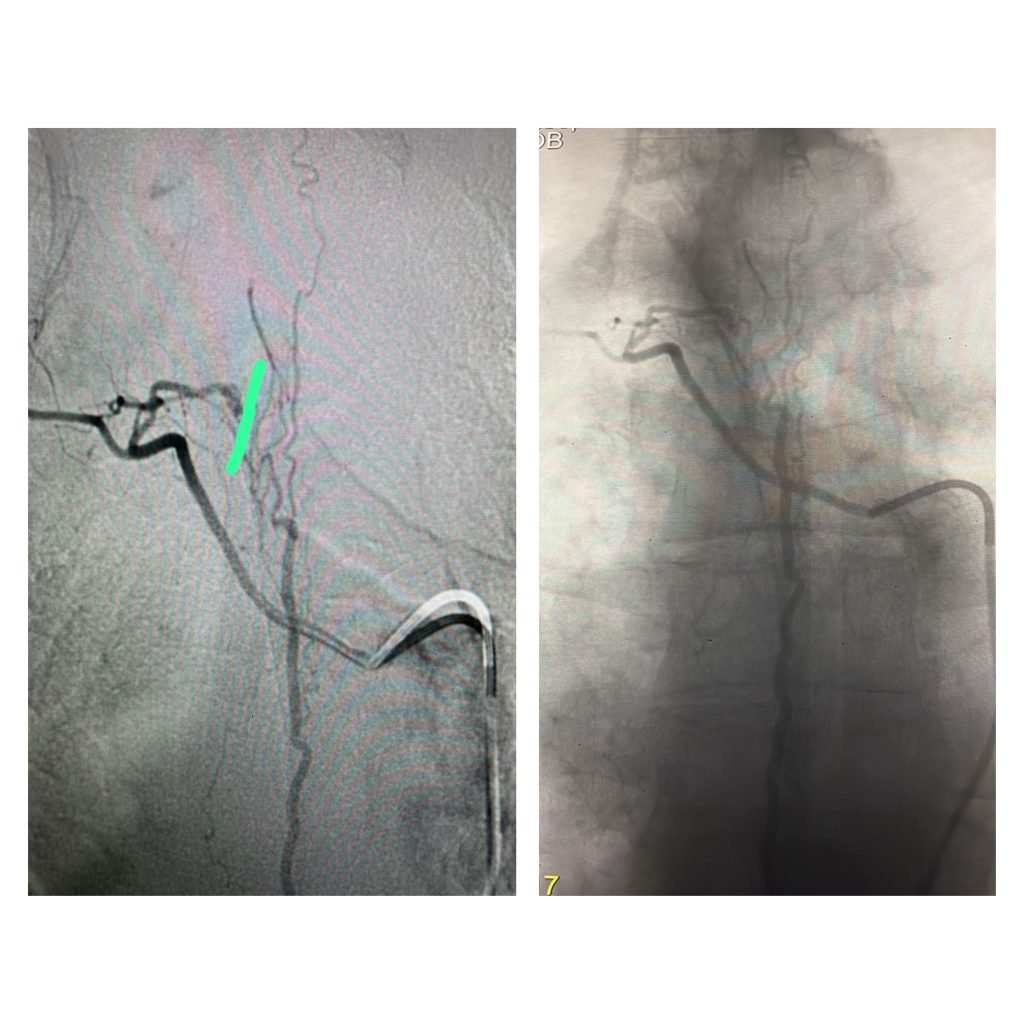

تمكّن الفريق الطبي في وحدة القسطرة بالمستشفى التخصصي، بقيادة الدكتور حازم حبوب استشاري الاشعة التداخلية، من إجراء تداخل طبي متقدم لمعالجة حالة شلل طرفي ناتج عن وجود تشوه شرياني وريدي في النخاع الشوكي، وذلك تحت المراقبة الفسيولوجية العصبية الدقيقة.

وتمت العملية بنجاح من خلال استحضار الإمكانيات الحسية والحركية للمريض أثناء الإجراء، لتفادي أي مضاعفات محتملة.

ويُعد هذا التدخل الأول من نوعه الذي يُنفذ في وحدة القسطرة بالمستشفى، مما يعكس التقدم المستمر في مستوى الرعاية الطبية والتخصصية المقدّمة.

ومن الجدير بالذكر أن قسم القسطرة في المستشفى التخصصي يضم أحدث الأجهزة ومنها Philips Azurion 7 Flexarm الأحدث بالعالم والأول في الشرق الأوسط وجهازGE Innova الأول من نوعه في الأردن.